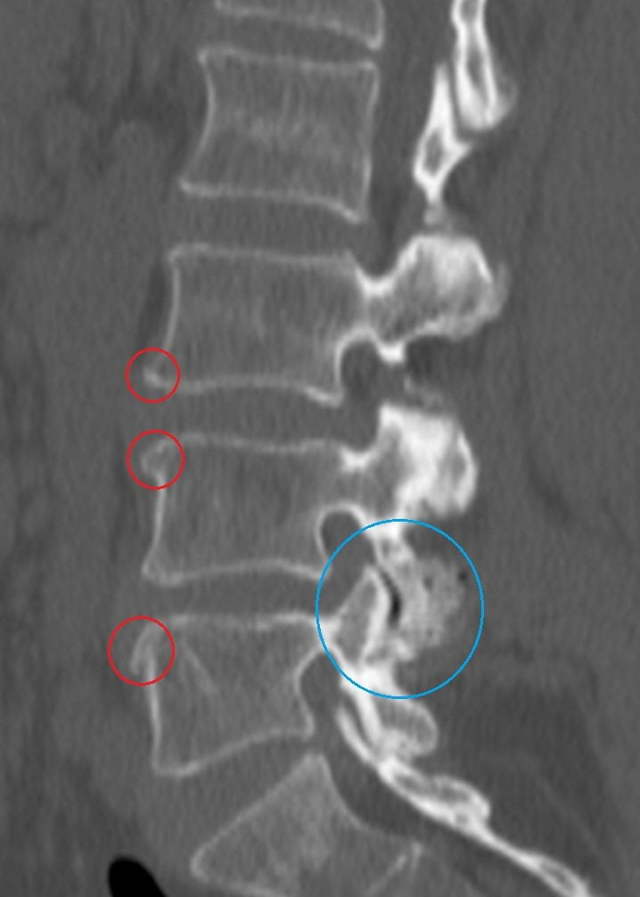

- рентгенография шейно-грудного отдела позвоночника в 2 проекциях;

- МРТ по показаниям.

Исключение сердечно-сосудистой патологии подтверждается отсутствием изменений на ЭКГ, которое может проводиться с нагрузкой и в динамике для оценки работы сердца. После обследования пациент направляется на консультацию к невропатологу и кардиологу с последующим выставлением диагноза и назначением лечение.

Некоторую информацию об изменениях может дать рентгенография. Для уточнения локализации поражения в позвоночнике и степени остеохондроза применяются МРТ или КТ. Послойное изображение помогает достоверно определить все проблемы с телами позвонков и дисками между ними.